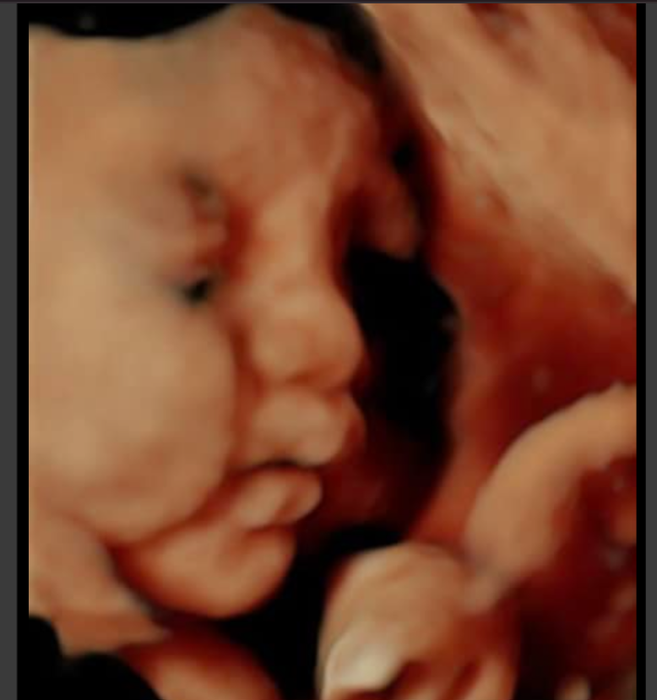

ThS. Bs. Kiều Văn Đồng trực tiếp điều hành phòng khám và theo dõi sát sao sức khỏe của mẹ và bé. Bác sĩ hiện đang là trưởng khoa sản tại Bệnh viện Bưu Điện với hơn 30 năm kinh nghiệm trong lĩnh vực sản phụ khoa. Bác sĩ Đồng nổi bật với chuyên môn trong các lĩnh vực đỡ đẻ, mổ lấy thai, điều trị u xơ tử cung, u nang buồng trứng và u xơ vú, luôn cam kết mang đến chất lượng dịch vụ tốt nhất cho mẹ và bé. Phòng khám không ngừng cập nhật các kỹ thuật mới như chẩn đoán dị tật trước sinh, sinh không đau, và tư vấn điều trị cho các cặp vợ chồng hiếm muộn.

Phòng khám bác sĩ Kiều Văn Đồng không chỉ khám thai mà còn điều trị tất cả các bệnh lý liên quan đến thai kỳ và cung cấp dịch vụ sinh đẻ cho các mẹ. Phòng khám cung cấp gói chăm sóc thai kỳ bao gồm khám thai, theo dõi định kỳ, tư vấn dinh dưỡng, tâm lý và chuẩn bị cho quá trình sinh nở. Đặc biệt, phòng khám còn cung cấp dịch vụ đặt lịch hẹn trước, giúp mẹ bầu tiết kiệm thời gian và tránh phải chờ đợi lâu.